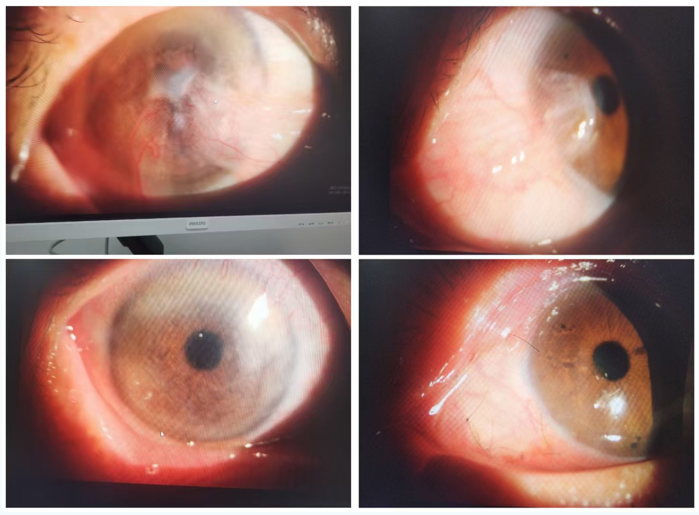

翼状胬肉切除

联合角膜缘干细胞移植术

耳部手术

开展耳部手术,包括耳道良性肿物切除术、鼓膜修补术、鼓膜切开术置管术、鼓室成型术、乳突根治术等,用于治疗耳道良性肿物、外耳/中耳胆脂瘤,鼓膜穿孔、分泌性中耳炎、慢性中耳炎等耳部疾病。

分泌性中耳炎治疗成果展示

治疗前和治疗后